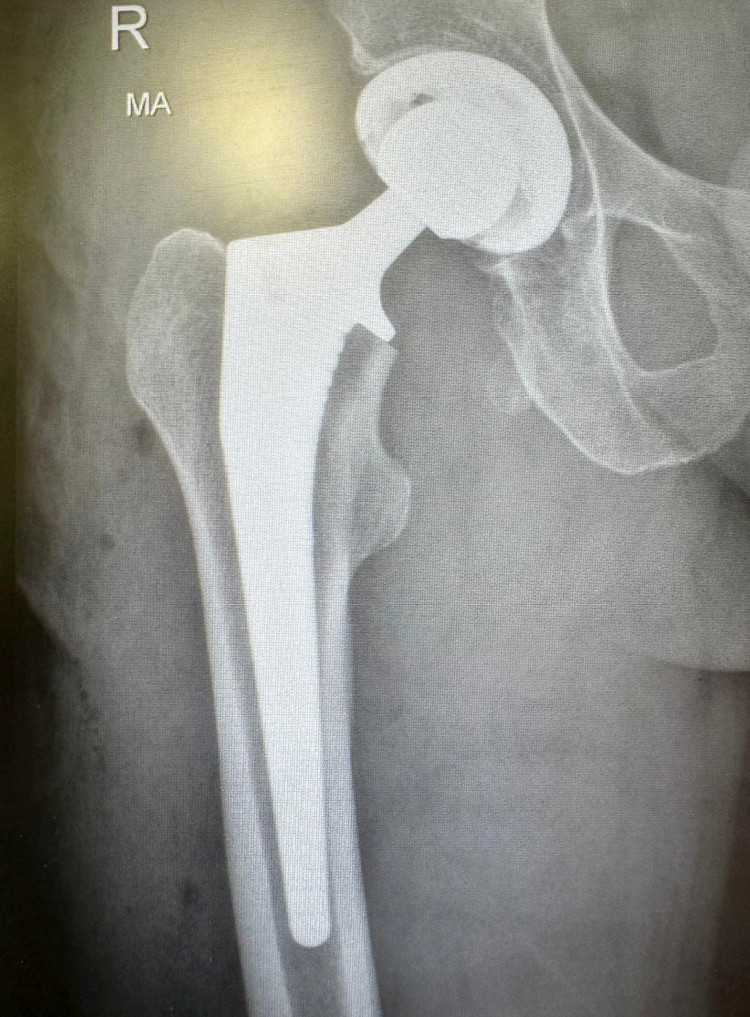

She was admitted to Warwick Hospital, where she underwent a three-hour hip replacement procedure the following day.

The operation was successful and she was released after spending a week in hospital.